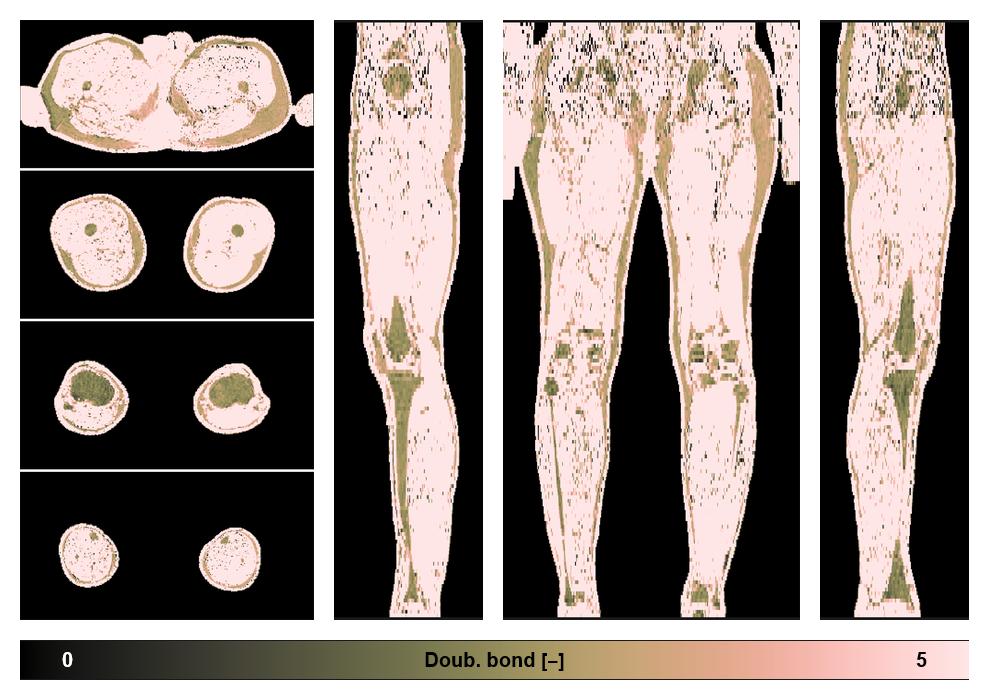

• Number of double bonds in subcutanious fat

Number of double bonds in subcutanious fat.